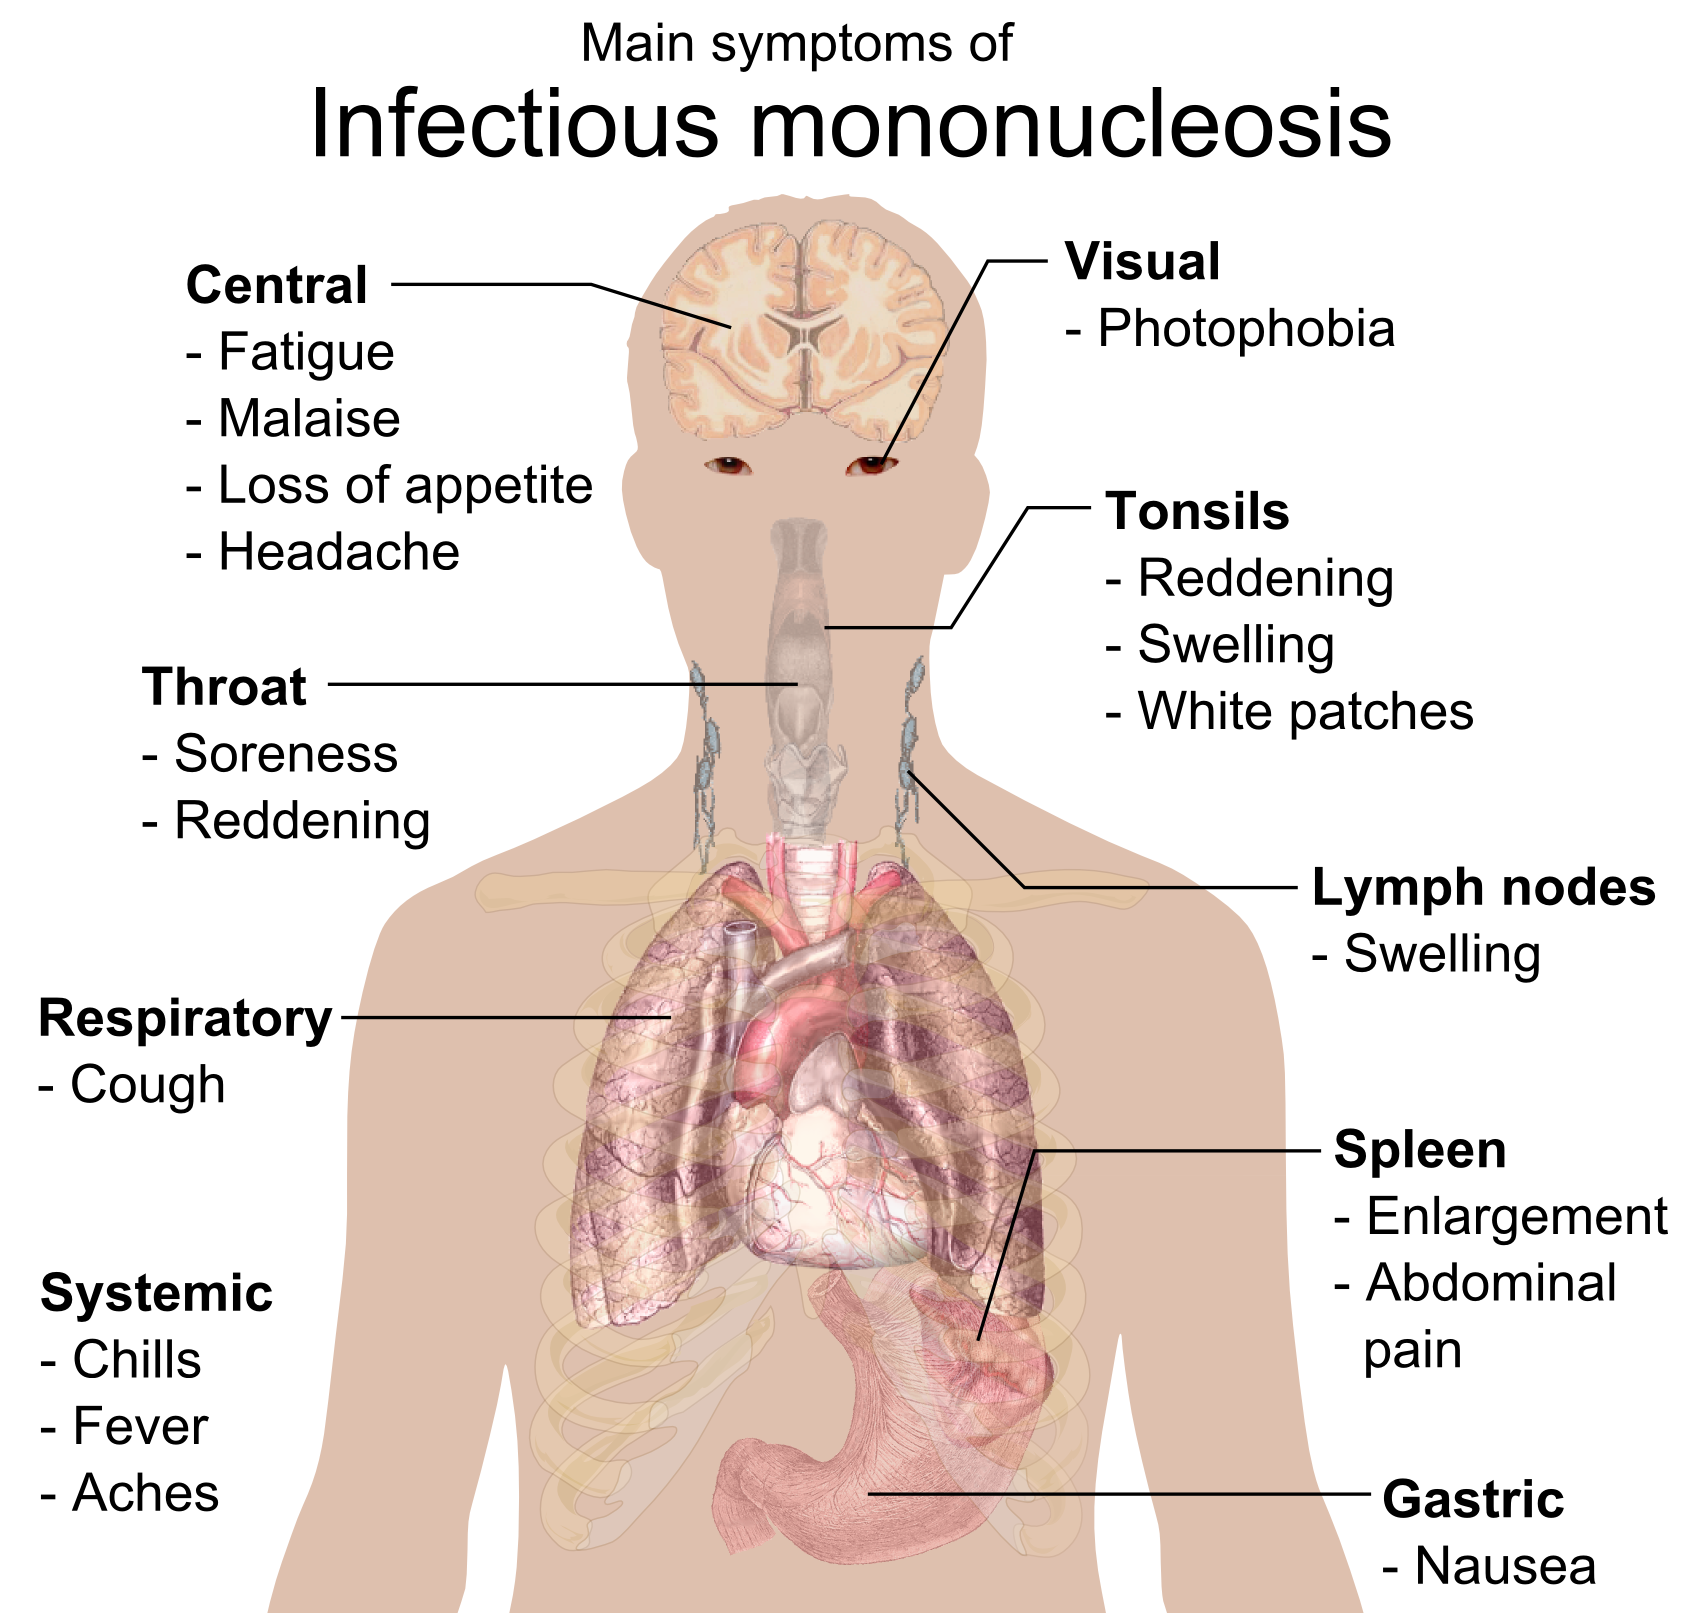

감염성 단핵구증은 엡스타인-바 바이러스(EBV)를 포함한 여러 원인에 의해 발생하는 질환으로, 발열, 인후통, 림프절 종창이 특징적인 증상이다. EBV가 가장 흔한 원인이며, 타액을 통해 전파된다. 소아는 무증상 또는 경미한 증상을 보이지만, 청소년 및 젊은 성인은 4~6주의 잠복기 후 피로감, 인후통, 림프절 비대 등의 증상을 겪을 수 있다. 진단은 신체 검사, 혈액 검사, 혈청학적 검사를 통해 이루어지며, 특이적인 치료법은 없고 대증 요법을 시행한다. 대부분 자연 치유되지만, 드물게 비장 파열, 신경계 합병증 등 심각한 합병증이 발생할 수 있다.

감염성 단핵구증의 의학적 징후와 증상은 연령에 따라 다르게 나타난다.[94]

- '''청소년기와 젊은 성인'''의 경우, 이 질병은 발열, 인후통, 림프절 부종의 세 가지 특징적인 증상으로 나타난다.[17] 발열은 보통 14일 동안 지속되며, 종종 경미하다.[18][30] 인후통은 보통 3~5일 동안 심하며, 이후 7~10일 이내에 호전된다.[19] 림프절 부종은 움직일 수 있으며, 보통 목 뒤(후경부 림프절)에 위치하며 때로는 신체 전체에 나타난다.[11][20][30]

- '''소아'''의 경우 엡스타인-바 바이러스에 감염되어도 대부분 증상이 없거나 가볍다.[94]

- '''고령층'''의 경우 인후통과 림프절병증과 같은 특징적인 징후와 증상을 덜 나타내며, 대신 주로 장기간의 발열, 피로, 권태감, 신체 통증을 경험할 수 있다.[30][23]

이 질병의 가장 두드러진 징후는 종종 인두염이며, 이는 비대해진 편도와 고름이 동반되는 경우가 많으며, 이는 연쇄상구균성 인두염의 경우와 유사한 삼출물이다.[30]

3. 1. 소아

신생아나 소아는 엡스타인-바 바이러스에 감염되어도 대부분 증상이 없거나 가볍다.[94] 후진국이나 개발도상국 혹은 위생 상태가 좋지 않은 환경에서는 대부분 신생아나 소아기에 엡스타인-바 바이러스에 감염되기 때문에 청소년기나 성인이 되어 감염되는 경우는 거의 없다.[94] 사춘기 이전에는 이 질병은 일반적으로 독감과 유사한 증상만 나타나거나, 전혀 나타나지 않을 수 있다.[15] 증상이 나타나는 경우, 일반적인 인후염과 유사한 경향이 있다(경미한 인두염, 편도염 동반 여부).[30]1~2세 정도의 어린아이의 첫 감염에서는 발열과 구개 편도의 농전 (백태)을 동반한 종창·발적이 보이는 정도로, 특이적인 증상이 두드러지지 않는 경우가 많다. 이 때문에 이 연령대의 아이의 첫 감염에서는 전염성 단핵구증으로 진단되지 않고 "편도염"으로 진단되는 경우가 많은 것으로 보인다. 2~3일 만에 자연적으로 호전되기 때문에, 그 이상의 추적도 거의 이루어지지 않는 것으로 보인다.

3. 2. 청소년 및 젊은 성인

청소년이나 젊은 성인이 엡스타인-바 바이러스에 감염되면 4~6주간 증상이 없는 잠복기를 거친다. 이후 피로감, 권태감, 근육통이 1~2주 동안 나타난 후 발열, 인후통, 림프절 비대가 발생한다.[94] 림프절 부종은 주로 목 뒤쪽(후경부 림프절)에서 나타나지만, 때로는 신체 전체에서 나타나기도 한다.[11][30][20]주요 증상으로는 피로감이 있다.[2] 두통, 복통, 구역질, 구토도 나타날 수 있다.[17] 대부분의 증상은 2~4주 후에 사라지지만,[2][24] 피로감과 전반적인 불쾌감(권태감)은 몇 달 동안 지속되기도 한다.[30] 피로감은 환자의 약 28%에서 한 달 이상 지속되며,[21] 미열, 목 림프절 부종, 신체 통증 또한 4주 이상 지속될 수 있다.[30][22][23] 대부분의 사람들은 2~3개월 안에 일상생활로 복귀한다.[22]

가장 두드러진 증상은 인두염이며, 비대해진 편도와 고름이 동반되는 경우가 많고, 이는 연쇄상구균성 인두염과 유사한 삼출물이다.[30] 약 50%의 경우, 입천장에 점상 출혈이라고 하는 작고 붉은 자줏빛 반점이 나타날 수 있다.[23]

일부 환자들은 팔이나 몸통에 반점 또는 구진 형태의 발진이 나타난다.[30] 아목시실린이나 암피실린을 투여받은 거의 모든 환자에게서 전신적인 가려움증을 동반한 반점 구진성 발진이 나타나지만, 이것이 페니실린에 대한 과민반응을 의미하지는 않는다.[30][24]

3. 3. 고령층

고령자가 감염성 단핵구증에 걸리는 경우, 인후통과 림프절병증과 같은 특징적인 징후와 증상을 덜 나타낸다.[30][23] 대신, 주로 장기간의 발열, 피로, 권태감, 신체 통증을 경험할 수 있다.[30] 간 비대와 황달이 발생할 가능성이 더 높다.[23] 40세 이상은 심각한 질병으로 발전할 가능성이 더 높다.[31]3. 4. 합병증